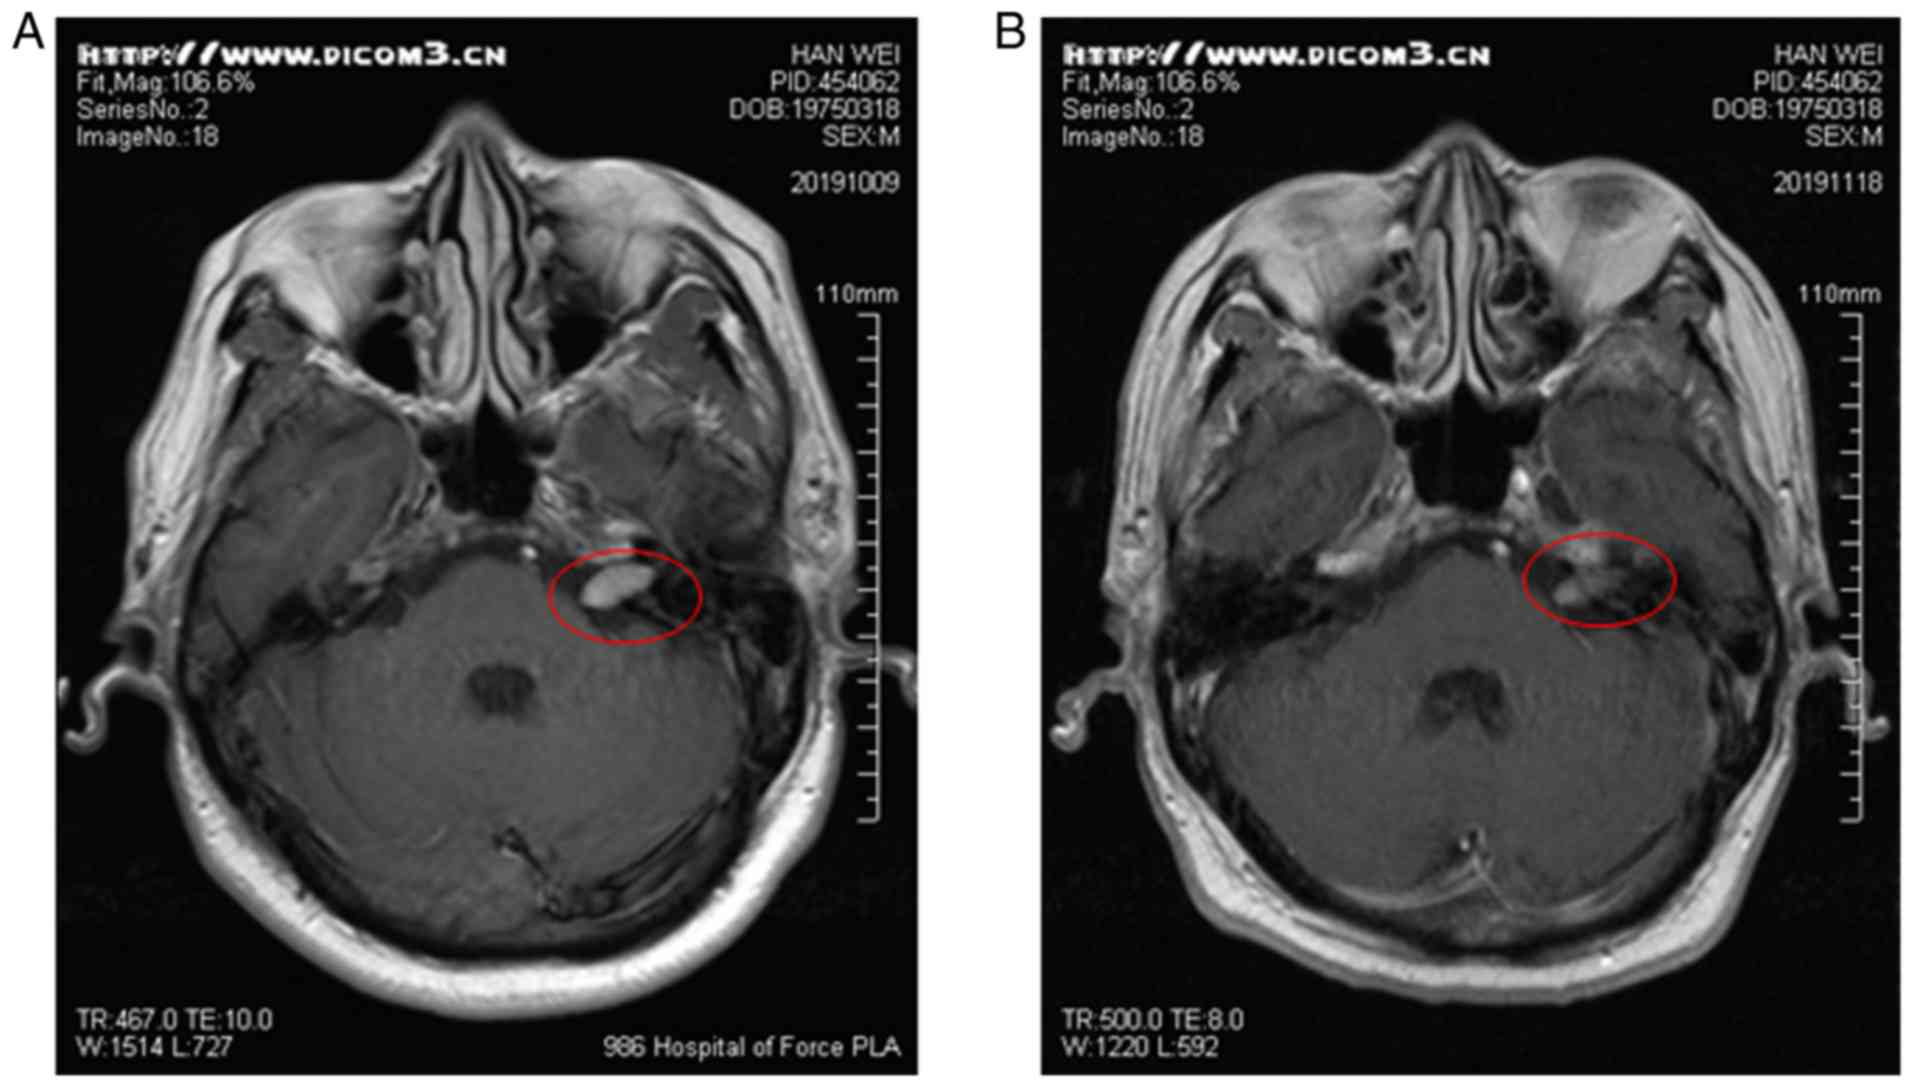

A 44-year-old male was diagnosed with extensive-stage small-cell lung cancer (ES-SCLC) accompanied by bone, brain and mediastinal lymph node metastasis. Between March, 2019 to August, 2019, he received systemic treatment with 6-cycle etoposide and cisplatin (EP) chemotherapy (etoposide 165 mg/m2 on days 1-3, and cisplatin 50 mg/m2 on days 1-2) followed by 200 mg pembrolizumab (Keytruda®, Merck Sharp & Dohme Corp.) intravenously once every 3 weeks, and the curative efficacy was evaluated as progressive disease (PD). He arose with facial paralysis, facial numbness, pain, tinnitus and limb joint pain on September 23, 2019 (Fig. 1A), although he had tendon reflexes. An enhanced cranial MRI examination revealed that there were abnormal enhancement areas in the left pontine crus, with clear boundaries (Fig. 2A). Facial nerve thickening and swelling caused facial paralysis. According to the toxicity grade, it was classified as grade 2. Thus, the use of pembrolizumab was terminated, although EP chemotherapy continued and he was treated with high-dose hormone therapy with the resolution of neurological symptoms. Methylprednisolone at 40 mg was administered for 5 days and he was then treated with oral prednisone tablets (25 mg). After 1 week, his facial symptoms were significantly alleviated (Fig. 1B). Following hormone therapy, the re-examination of the head MRI revealed that the lesion had shrunk and symptoms had improved (Fig. 2B). Subsequently, he was treated with etoposide/tenoposide alone, and he did not exhibit any signs of neurotoxicity. After completing the whole chemotherapeutic regimen, the primary tumor had markedly shrunk when comparing pre-treatment (Fig. 3A) and post-treatment (Fig. 3B).